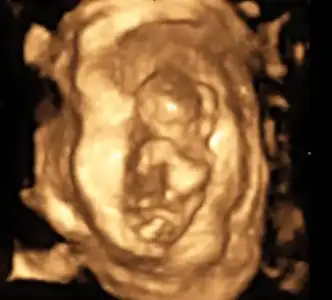

Merhaba, ultrason görüntülerinde sat'a göre 11+4 üz.

cinsiyet tahmini yapabilecek olan var mı:)